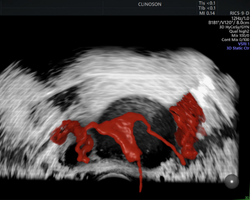

Hoje, atuo ajudando mulheres a terem diagnósticos precisos e tratamentos modernos, incluindo o cuidado e diagnóstico de miomas uterinos, fertilidade e acompanhamento na medicina fetal.

Também, especializei-me em métodos como a ultrassonografia avançada para endometriose e o HyCoSy — um exame moderno e menos invasivo que traz conforto, precisão e segurança para mulheres que enfrentam dificuldades como infertilidade e dores pélvicas.

- Especialista em tratamentos de miomas uterinos

- Pioneiro na realização de HyCoSy – Histerossonossalpingografia com contraste de microbolhas em Porto Alegre

- Pioneiro na realização de ablação por Radiofrequência para miomas uterinos no Rio Grande do Sul e em Santa Catarina